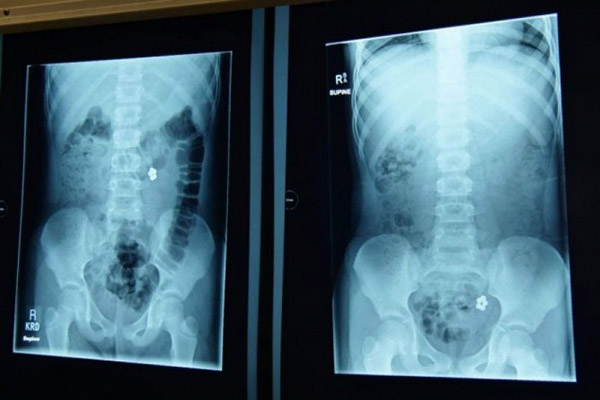

அங்கு சிறுமி ஒலிவியாவுக்கு மருத்துவர்கள் ஸ்கேன் செய்து அதன் அறிக்கையை பார்த்த போது அ திர்ச்சியடைந்தனர். காரணம் சிறிது சிறிதான காந்த உருண்டைகளை அவர் அதிகளவில் விழுங்கியதும் அது செரிமானம் ஆகும் இடத்தில் சிக்கி கொண்டதும் அதில் தெரியவந்தது.

அதே நேரத்தில் வேறு ஒரு சி றுவனும் காந்த உருண்டைகளை விழுங்கியதாக அங்கு வந்திருந்தான். இருவருக்கும் உடனடியாக சிகிச்சையளித்த மருத்துவர்கள் காந்த உருண்டைகளை போ ராடி வெளியில் எடுத்தனர்.